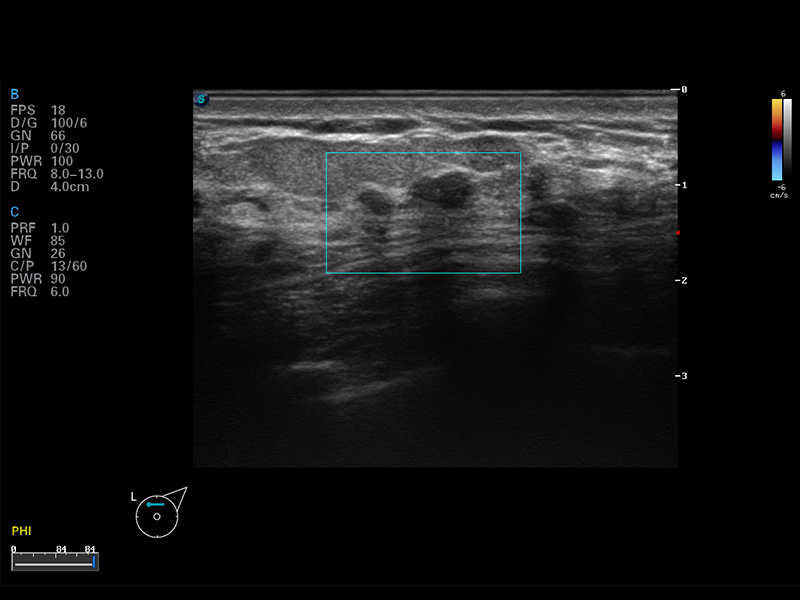

便携式彩色多普勒超声诊断仪

S8 EXP便携式彩色多普勒超声诊断仪是美狮贵宾会官网研发的高端全身应用型便携彩超。高通道的VIS平台融合可视化(Visual)、智能化(Intelligent)和人性化(Smart)的特点,配以美狮贵宾会官网自主研发生产的探头大家族,使您能够快速、准确的获得病人信息,提高工作效率的同时减轻疲劳。